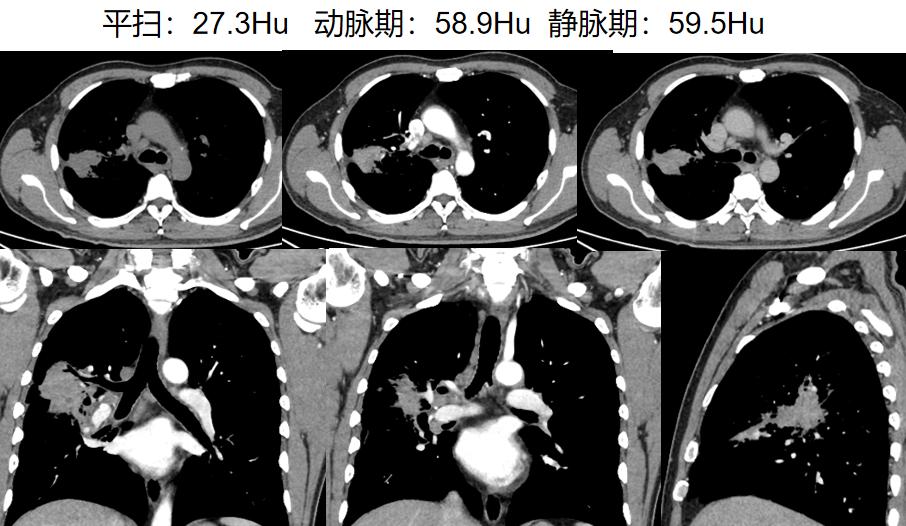

病例二

病史:女性,70岁。主诉:查体发现右肺上叶占位1周余。

影像描述:右肺上叶尖段见一不规则形混合磨玻璃密度灶,大小约 .7X4.2X4.5m,内可见多发小空腔中央部分较密实,周边可见斑片状密度增高影及毛刺,边界不清,邻近胸膜受牵拉,增强扫描实性成分可见强化:双肺另见多发点状结节灶,边界尚清,增强扫描未见明显强化。左肺上叶舌段见条索状密度增高灶,邻近胸膜受牵拉。段及以上支气管通畅。食管胸下段、胃责门及小弯侧胃壁略显增厚。纵隔内未见异常增大的淋巴结。双侧胸腔未见明显液性密度灶。

影像诊断:右肺上叶混合磨玻璃灶,鉴别于肺癌与机化性肺炎,建议病理学检查:双肺多发点状结节灶,建议随诊复查:

病理:腺癌。